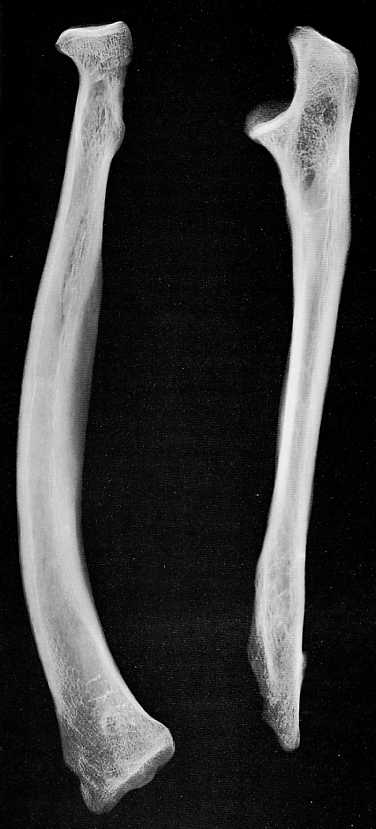

Malgré la présence fréquente d'ossements animaux ( parfois pathologiques) mélangés aux vestiges osseux humains étudiés, le laboratoire a [par manque de temps et de spécialistes] peu consacré de travaux à la paléopathologie animale, bien qu' ayant présenté, dès 1972, un cas intéressant d'exostose isolée appartenant à un Machairodus ( gisement de Senèze, Haute - Loire) [22]. Cet os pathologique, un humérus droit, montre sur la face latérale de sa diaphyse une excroissance volumineuse bifide, a la jonction des 1/3 supérieur et moyen, au niveau de la crête deltoïdienne. La partie supérieure dirigée vers le bas, forme un bec irrégulier, pointu, légèrement érodé vers son extrémité. Les caractéristiques radiologiques ( homogénéité nette de l’os médullaire et périmédullaire) permettent d’en faire une exostose isolée véritable. Une telle formation osseuse peut obéir à deux étiologies différentes, entre lesquelles il n’a pas été possible de trancher, à savoir :